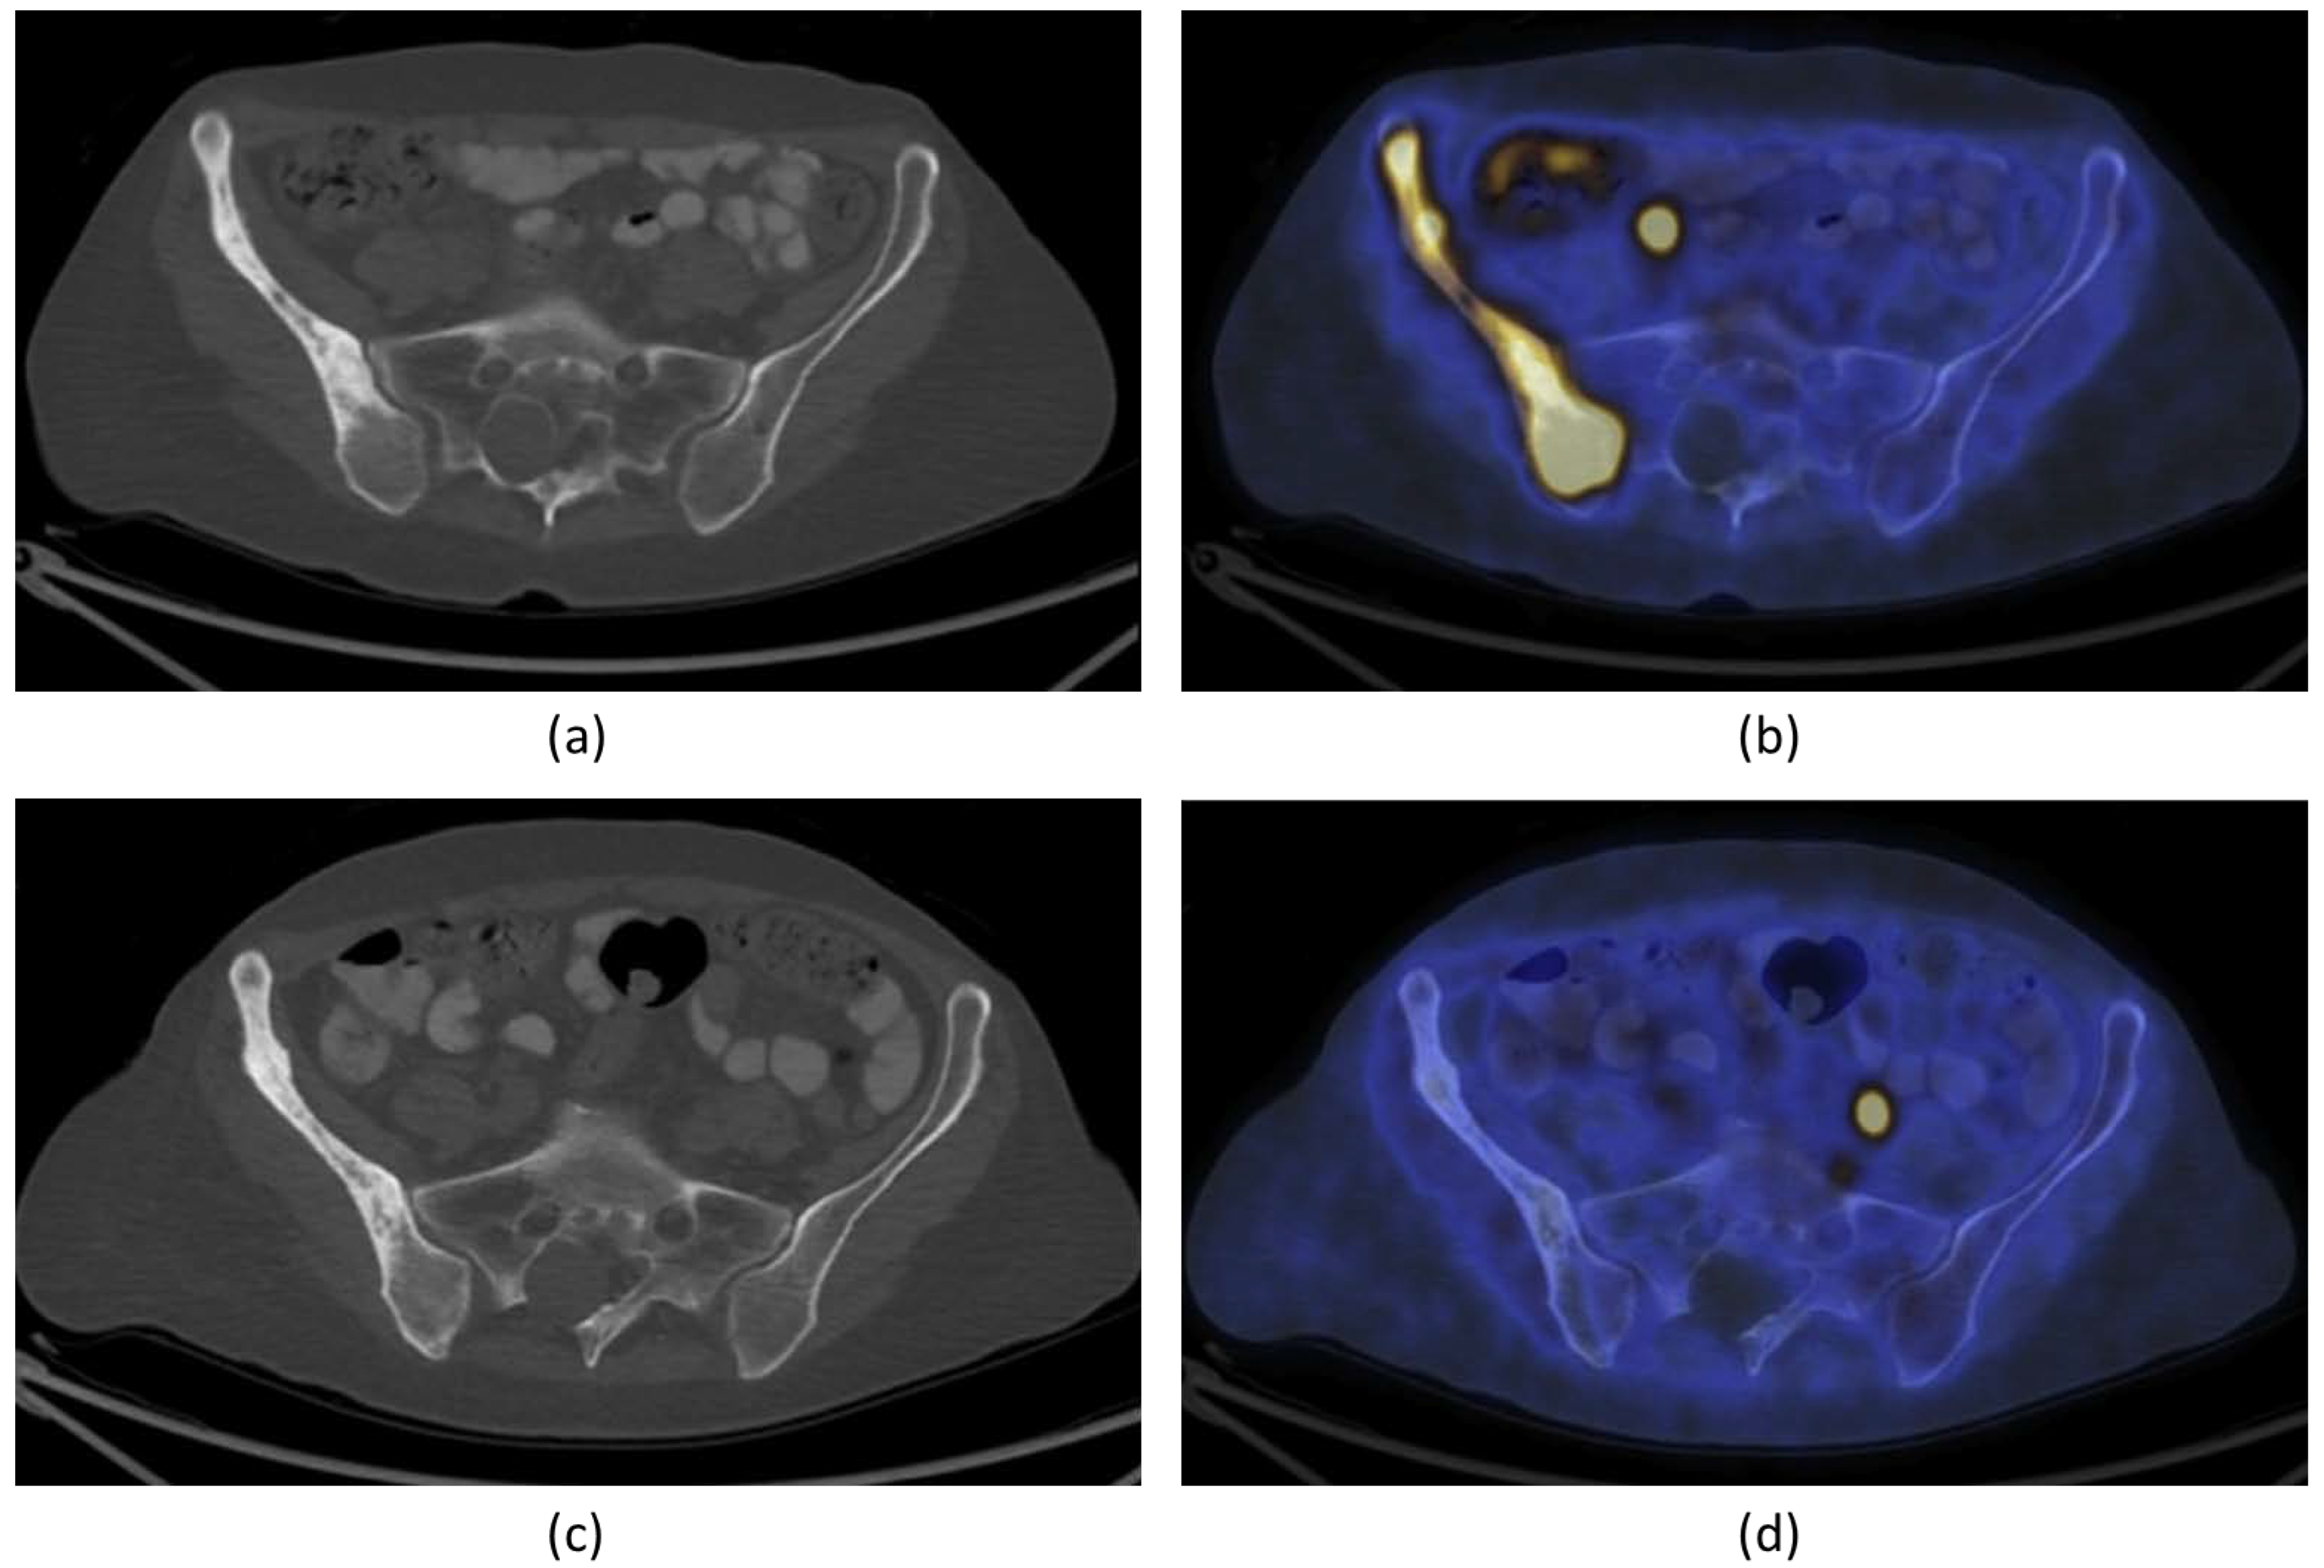

Figure 5.

A 66-year-old woman with bone metastasis in the right ilium. Trans-axial 18F-FDG PET/CT slide at the level of the pelvis (a): CT; (b): fused PET/CT) demonstrates pathological increase in 18F-FDG uptake in a larger mixed lytic-sclerotic lesion before treatment. After MR-HIFU treatment, no 18F-FDG uptake was observed in the right ilium (d). There is, however, no change in the bony structure on CT (c). The findings are consistent with healed metastasis in the right ilium with no evidence of active residual malignancy in the site. FDG = fluorodeoxyglucose; PET = positron emission tomography; CT = computed tomography). Figures adapted and reprinted from Journal of Pain and Symptom Management, Volume 56 Issue 1, Eisenberg E, Shay L, Keidar Z, Amit A, and Militiau D, Magnetic Resonance–Guided Focused Ultrasound Surgery for Bone Metastasis: From Pain Palliation to Biological Ablation?, 158–162, 2018, with permission from Elsevier (Amsterdam, The Netherlands) [32].